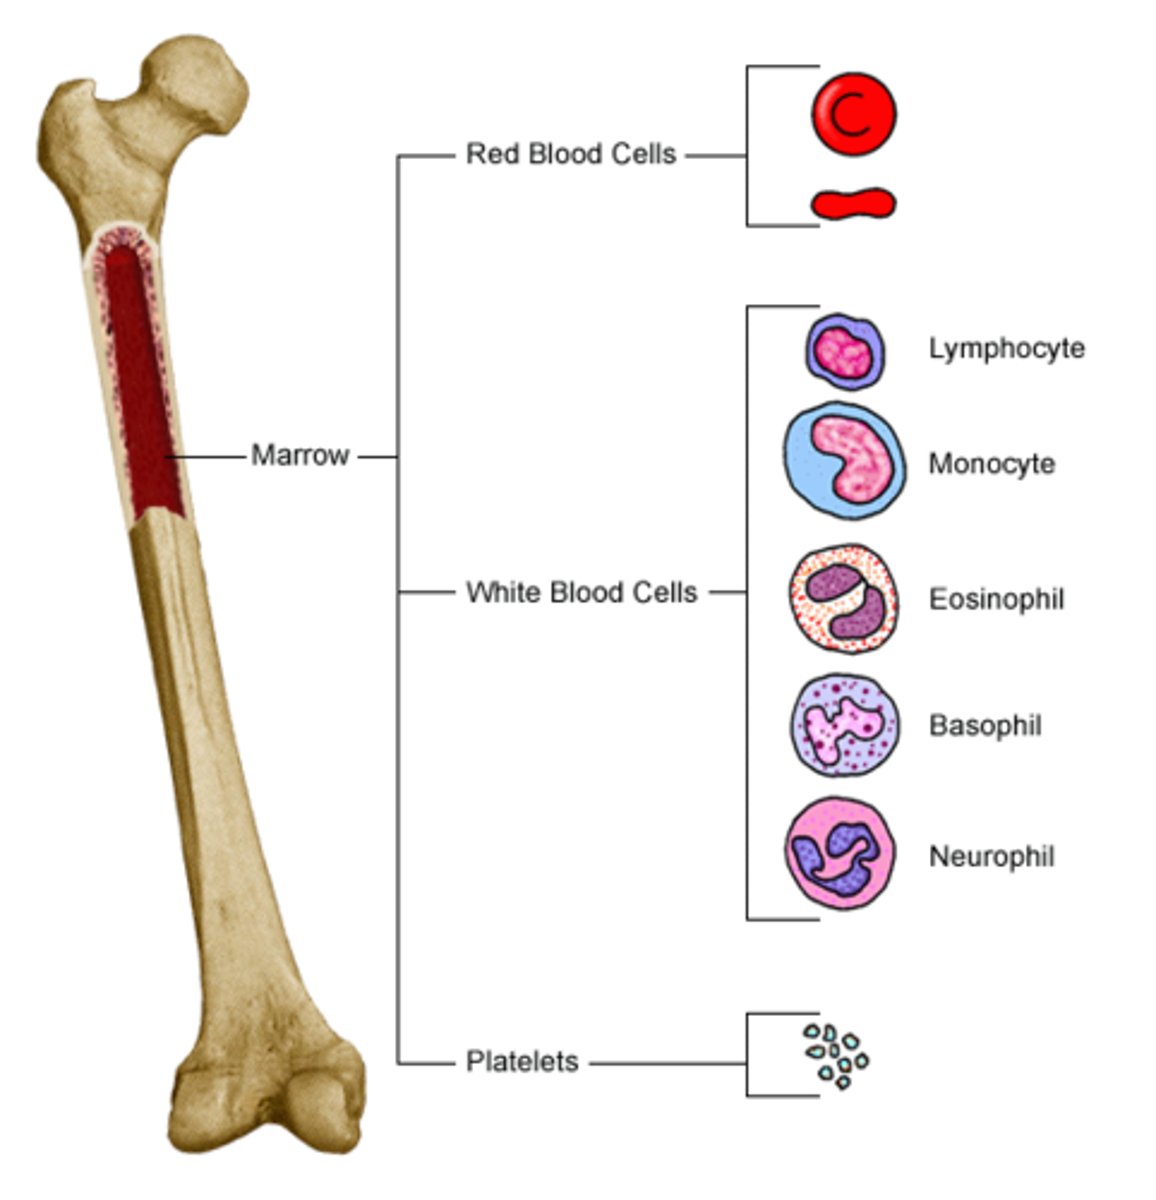

Hematopoiesis

The formation of blood cells from stem cells in the bone marrow

Leukocytes

White blood cells

Granular leukocytes

Neutrophils, eosinophils, basophils

Agranular leukocytes

Lymphocytes and monocytes

Neutrophils

Structure: Nuclei has three or more lobes, granules stain light pink

Function: The most common WBC; fights bacterial infections by engulfing bacteria by phagocytosis

Eosiniphils

Structure: Nuclei has two lobes, granules stain bright red

Function: A WBC that digests and destroys parasitic worms, they also play a role in allergy and immune response

Basophils

Structure: Nuclei is U or S shaped but is obstructed by HUGE blue granules

Function: A WBC that produces histamine --> causing inflammation during an immune response

Monocytes

Structure: Largest WBCs, U shaped nucleus

Function: A large WBC that transform into macrophages to fight off viruses and chronic infections

Lymphocytes

Structure: Has a large, dark purple nucleus that takes up most of the cell volume

Function: B cells make antibodies, T cells fight off viral infections, NK cells